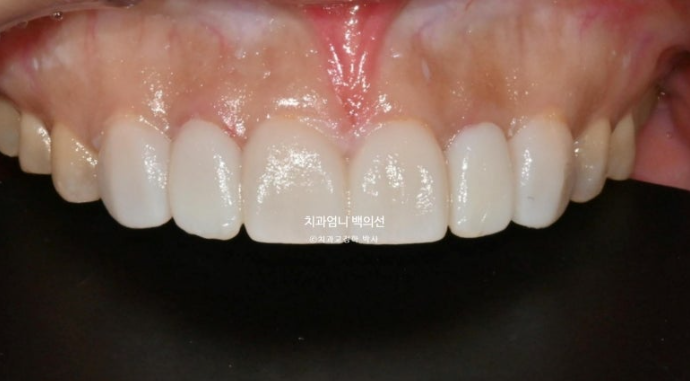

피팅 모습입니다.

이 상태에서 환자분의 니즈를 더해 젤라미 제작에 들어갑니다.

젤라미 제작은 10일이 걸립니다.

젤라미 부착 후 모습입니다.

24.11

앞니 깨진 부분이 깔끔하게 회복되었습니다.

100% 무삭제로 진행했습니다.